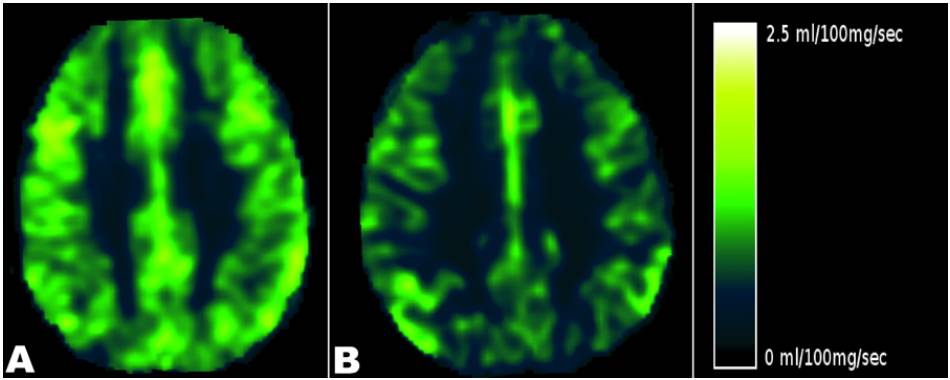

CCSVI appears to strongly influence two pivotal aspects of brain pathophysiology: parenchymal perfusion and cerebrospinal fluid (CSF) flow. CCSVI affects the venous return and MRI studies have shown that it is strongly associated with hypoperfusion of brain parenchyma, (Figure 3). Interestingly, this has consistently been described in multiple sclerosis patients yet the autoimmune theory of the disease cannot explain it. (15-16)